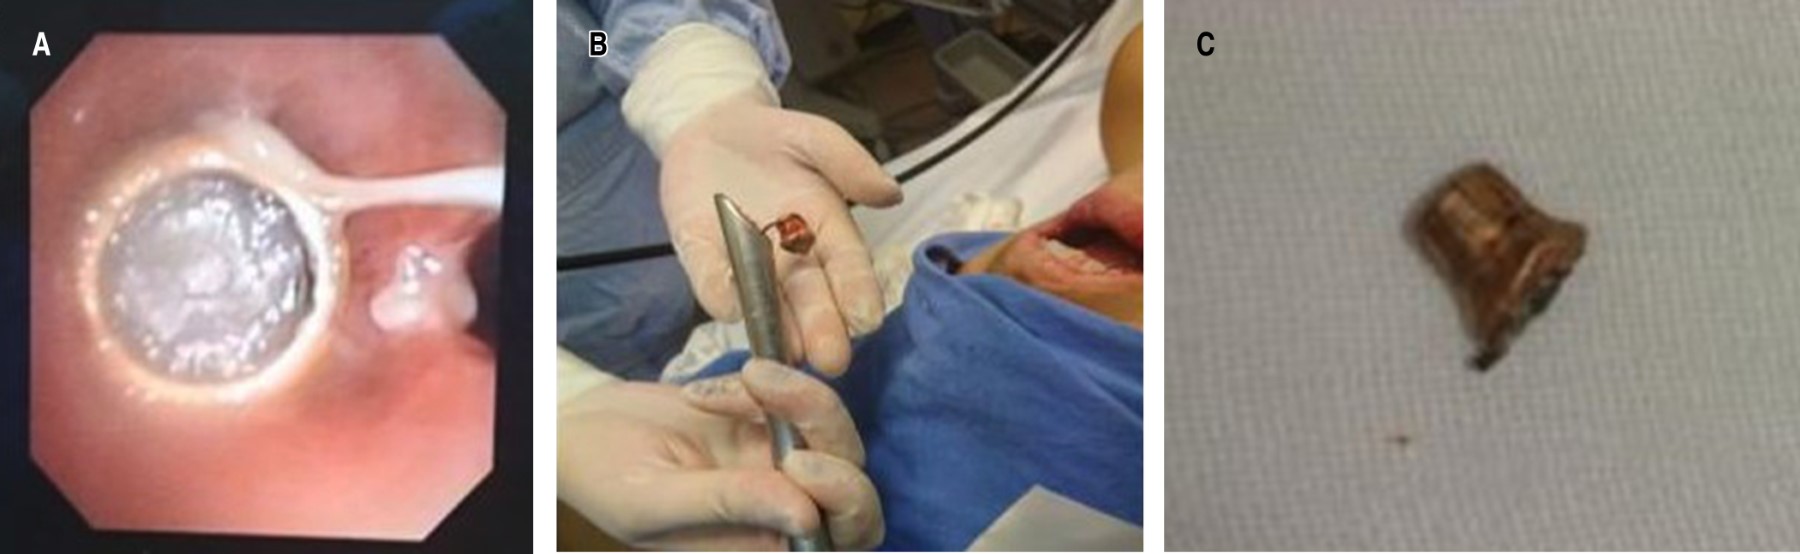

Es interconsultado nuestro instituto donde se valora como cuerpo extraño alojado en bronquio principal izquierdo con atelectasia pulmonar total ipsilateral. Se programa y se realiza broncoscopia flexible con videobroncoscopio 1T-180 Olympus, donde se observa el árbol bronquial con escasas secreciones espesas, se observa bronquio derecho libre y permeable y bronquio izquierdo con proyectil que obstruye el 100% de la luz. Se hace broncoscopia flexible a través de traqueoscopio de 12 mm (Storz) y canastilla de extracción de cuerpo extraño flexible (Boston Scientific), con lo cual se retira proyectil de arma de fuego, se hace aspiración de secreciones espesas del bronquio izquierdo para cultivo, con mucosa con inflamación sin datos de lesión de la pared bronquial y mucosa íntegra. Se egresa con saturación del 97% (Figura 3).

La clínica que los pacientes sin alteraciones en su estado mental presentan por aspiración de objetos a la vía aérea son tos y dificultad respiratoria, si este primer período es superado el paciente puede presentar estridor o sibilancias en donde se aloje el objeto. Si el cuadro avanza se condiciona atelectasia que evolucionan a infecciones de repetición o neumonías, hasta que no se sospecha o se evidencia el cuerpo extraño. En este caso por la sedación de la paciente no hubo cuadro de aspiración con tos o dificultad para respirar. Se presentaron datos de desaturación y un cuadro clínico compatible con atelectasia, se corroboró con una radiografía de tórax, que es el estudio de sospecha más importante tanto para observar la posición del cuerpo extraño como para evaluar las consecuencias del mismo como son las atelectasias o neumonías. La placa de tórax en este caso evidenció el objeto en el bronquio principal del lado izquierdo y la atelectasia total del pulmón ipsilateral.7

La evaluación del paciente con cuerpo extraño en vía aérea parte de la sospecha diagnóstica, por datos clínicos, se complementa con estudios de imagen como es la radiografía de tórax, pero el estándar de oro para su diagnóstico preciso y su tratamiento es la broncoscopia inicialmente flexible que también en algunos casos puede ayudar a la extracción del objeto y, si se requiere, una broncoscopia rígida, que es el procedimiento recomendado para la extracción de cuerpos extraños cuando por broncoscopia flexible no es posible por el tamaño y tipo de objeto. En el caso de nuestra paciente se evaluó la vía aérea por broncoscopia flexible y después mediante broncoscopio rígido se realizó la extracción del cuerpo extraño sin ninguna complicación, con lo cual se pudo evaluar las condiciones de la tráquea y bronquios para descartar lesiones o estenosis.8